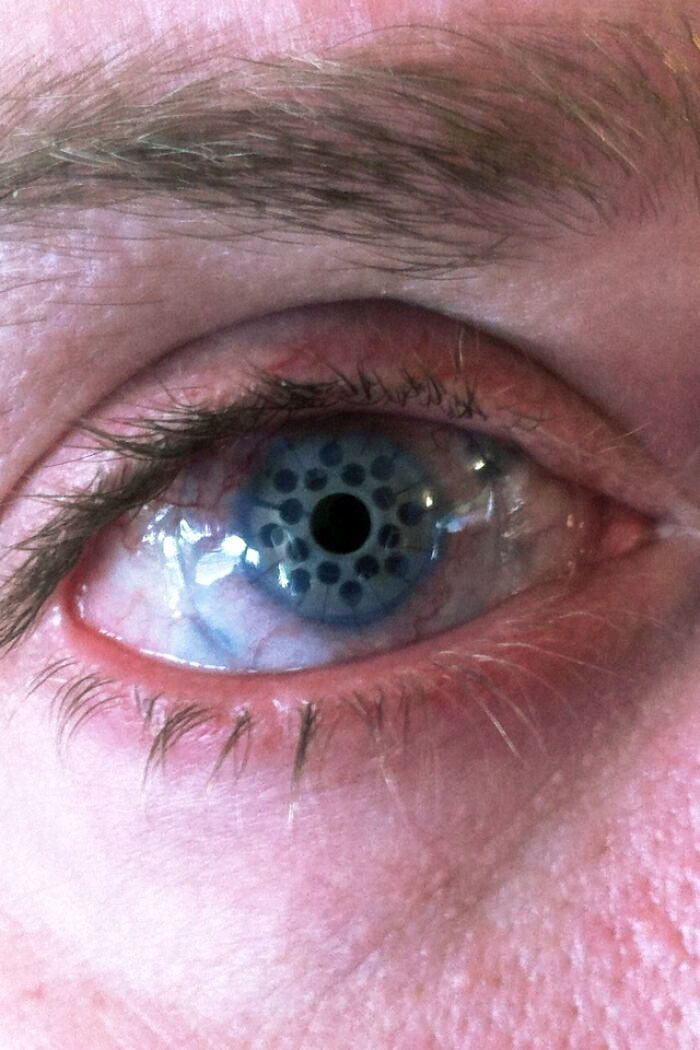

#2 Moje oko po transplantácii rohovky